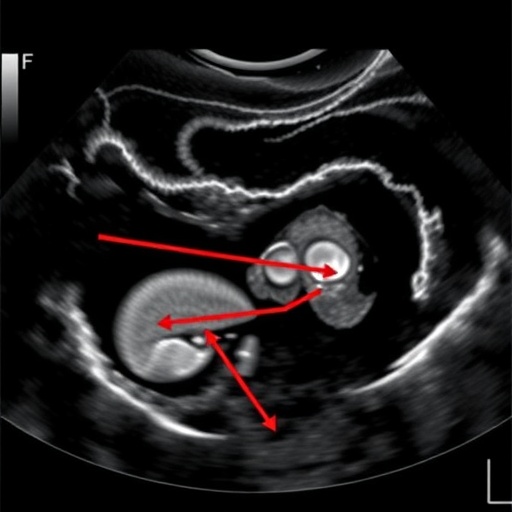

In their exploration, Lai et al. emphasize the clinical relevance of accurately diagnosing PBM at an early stage. Pancreaticobiliary maljunction is characterized by an abnormal connection between the pancreatic duct and the biliary system, leading to pancreatic juices entering the bile duct. This condition poses a risk for biliary cancers and acute pancreatitis, thereby prompting the need for timely intervention strategies. The urgency of the study is underscored by growing instances of PBM cases worldwide, particularly in young patients who are often undiagnosed.

The researchers employed a cohort of pediatric patients exhibiting symptoms indicative of biliary tract anomalies. The high-frequency ultrasonography employed harnesses advanced imaging techniques capable of revealing intricate details of the pancreaticobiliary architecture. Such precision in imaging can be vital for distinguishing PBM from other biliary pathologies, thus informing subsequent management decisions. The technology operates with greater clarity than standard ultrasound, reducing operator dependency while maximizing diagnostic accuracy.